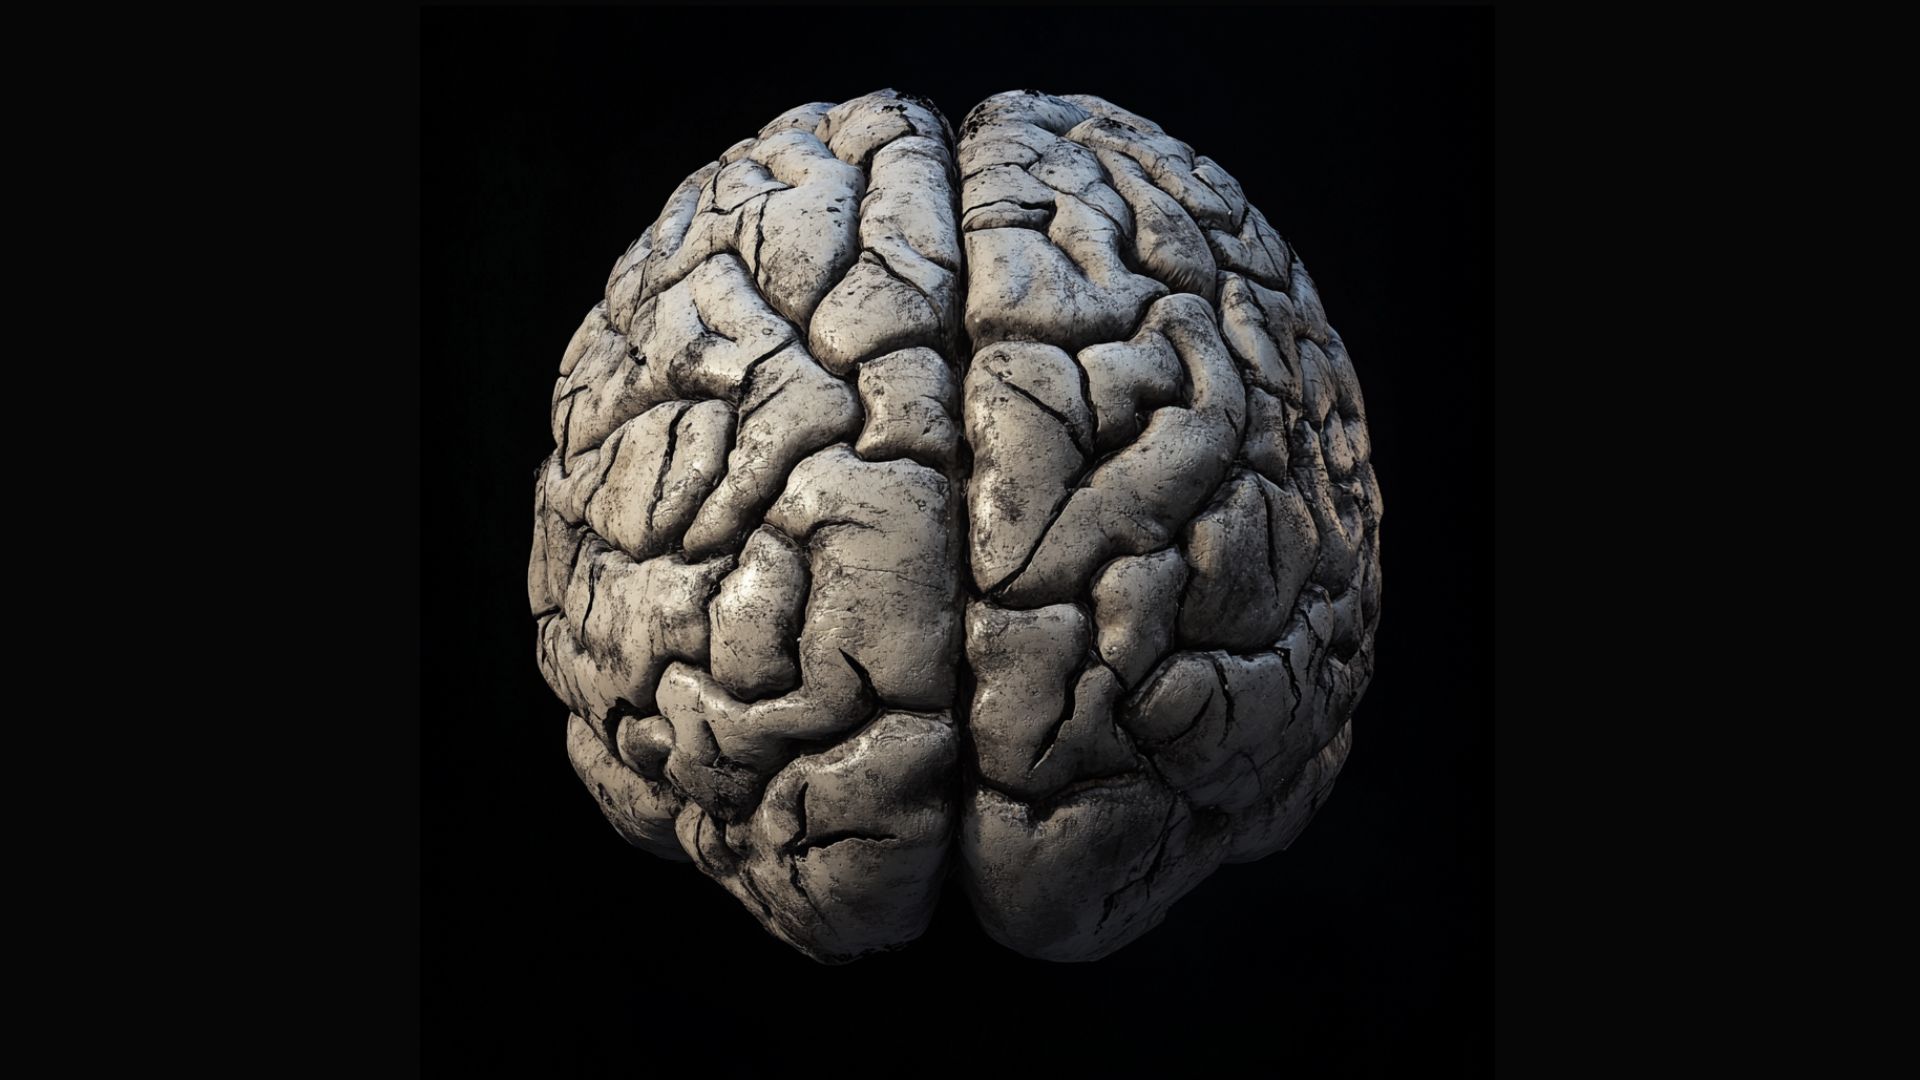

How predictive coding is changing our understanding of the brain

Below is an excellent article by Sage Briggs and here’s a link to a blog that relates to Predictive Coding: https://erikdalton.com/blog/cant-teach-experience-2/ How predictive coding is